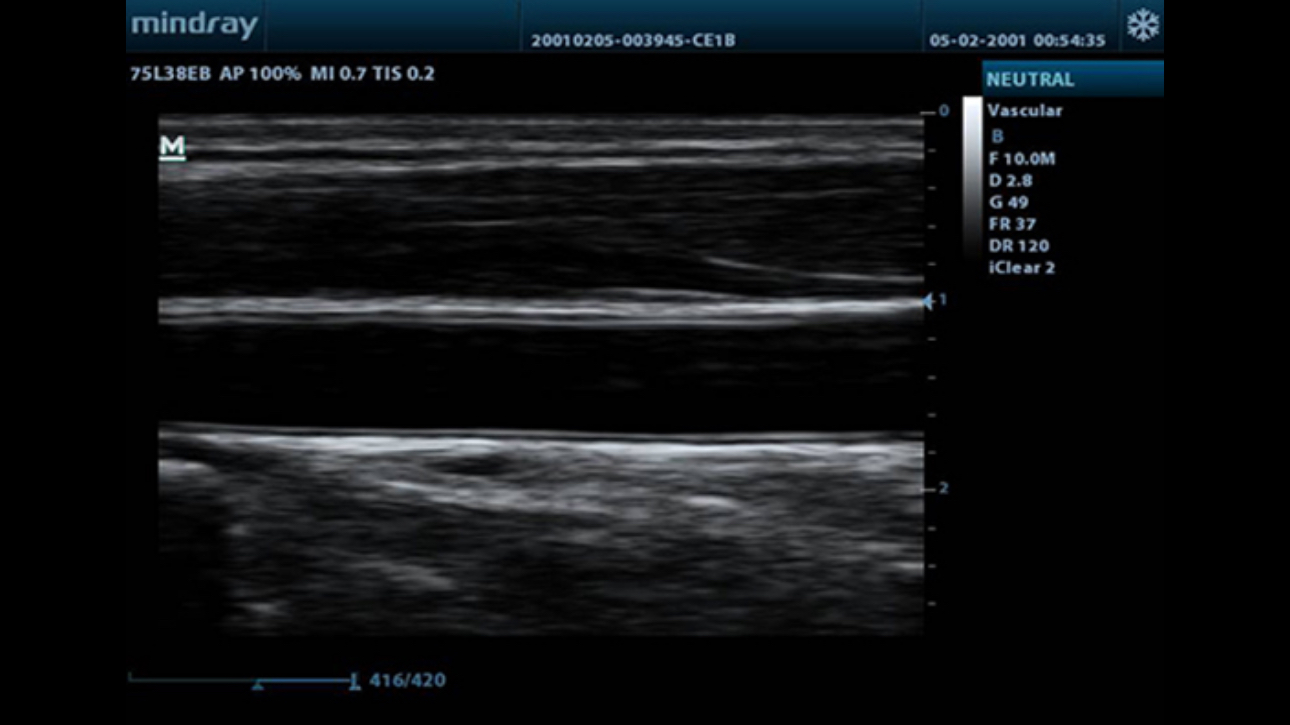

iClear?

Gain improved image quality based on auto structure detection.

- Sharper & Continuous Edges

- Smooth Uniform Tissues

- Cleaner ŌĆśno echo areasŌĆÖ